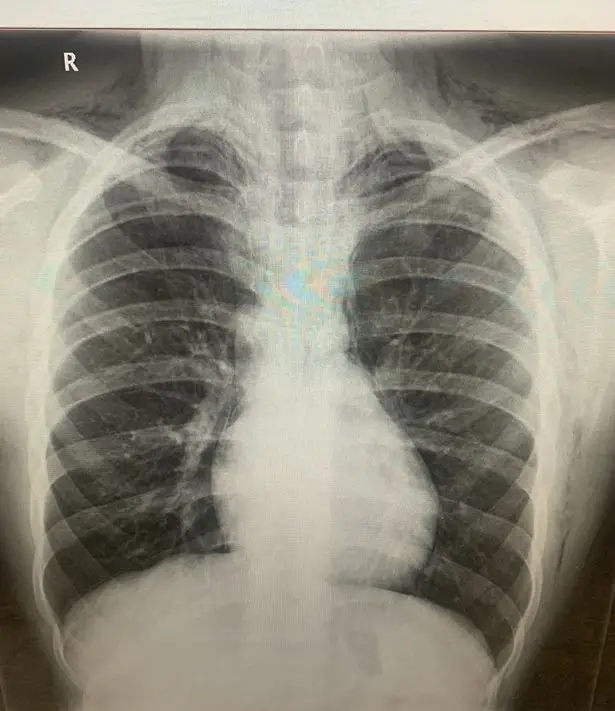

Earlier this year in June, a 16-year-old boy was said to be 'lucky to be alive' after he inhaled laughing gas and ended up being diagnosed with a ruptured lung as a result.

Alex Littler, a year 11 student from Cheshire, inhaled the nitrous oxide while at Parklife festival in Manchester (11-12 June).

He later complained of a swollen neck, breathlessness and feeling that his chest was like 'popping bubble wrap' when touched. Alex was rushed to hospital the following Monday, where he confessed to doctors and his mum that he'd inhaled the gas.

Alex was diagnosed with a ruptured and leaking lung, with medics telling him he was lucky to be alive but that he may have to undergo surgery to remove air that was trapped around his lungs and heart. Thankfully an oxygen mask left on overnight managed to remove the trapped air without Alex having to undergo an operation.